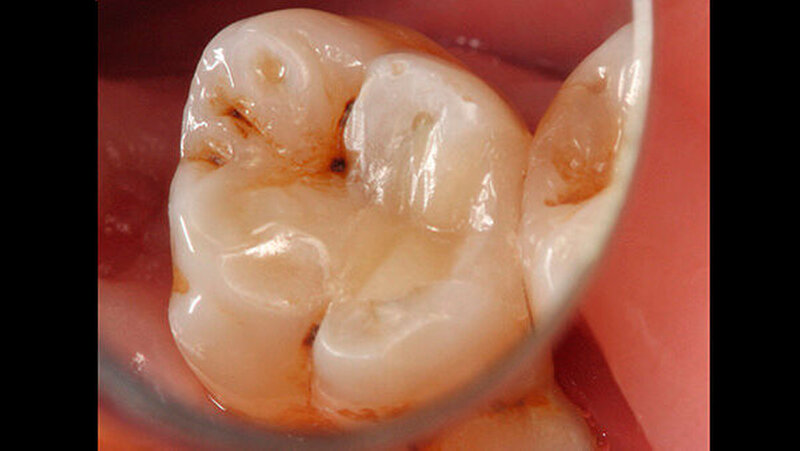

Das Zementmaterial wurde nach Herstellerangaben angemischt und mittels eines kleinen Kugelstopfers (Dycal-Instrument) im Bereich der distalen pulpalen Wand appliziert und mit einem Heidemann-Spatel adaptiert. Das Material wurde damit gleichzeitig sowohl zur Caries-profunda-Behandlung als auch zur Unterfüllung eingesetzt. Nach einer Abbindezeit für das Material von zwölf Minuten wurde der Defekt mit einer Kompositfüllung restauriert (Abbildung 4).

Anschließend erfolgte der Aufbau der Restauration in Inkrement-Technik. Nachdem der Kofferdam entfernt wurde, wurden Okklusion und Artikulation überprüft, und es erfolgten Ausarbeitung und Politur (Abbildung 8) mit Feinkorndiamanten.